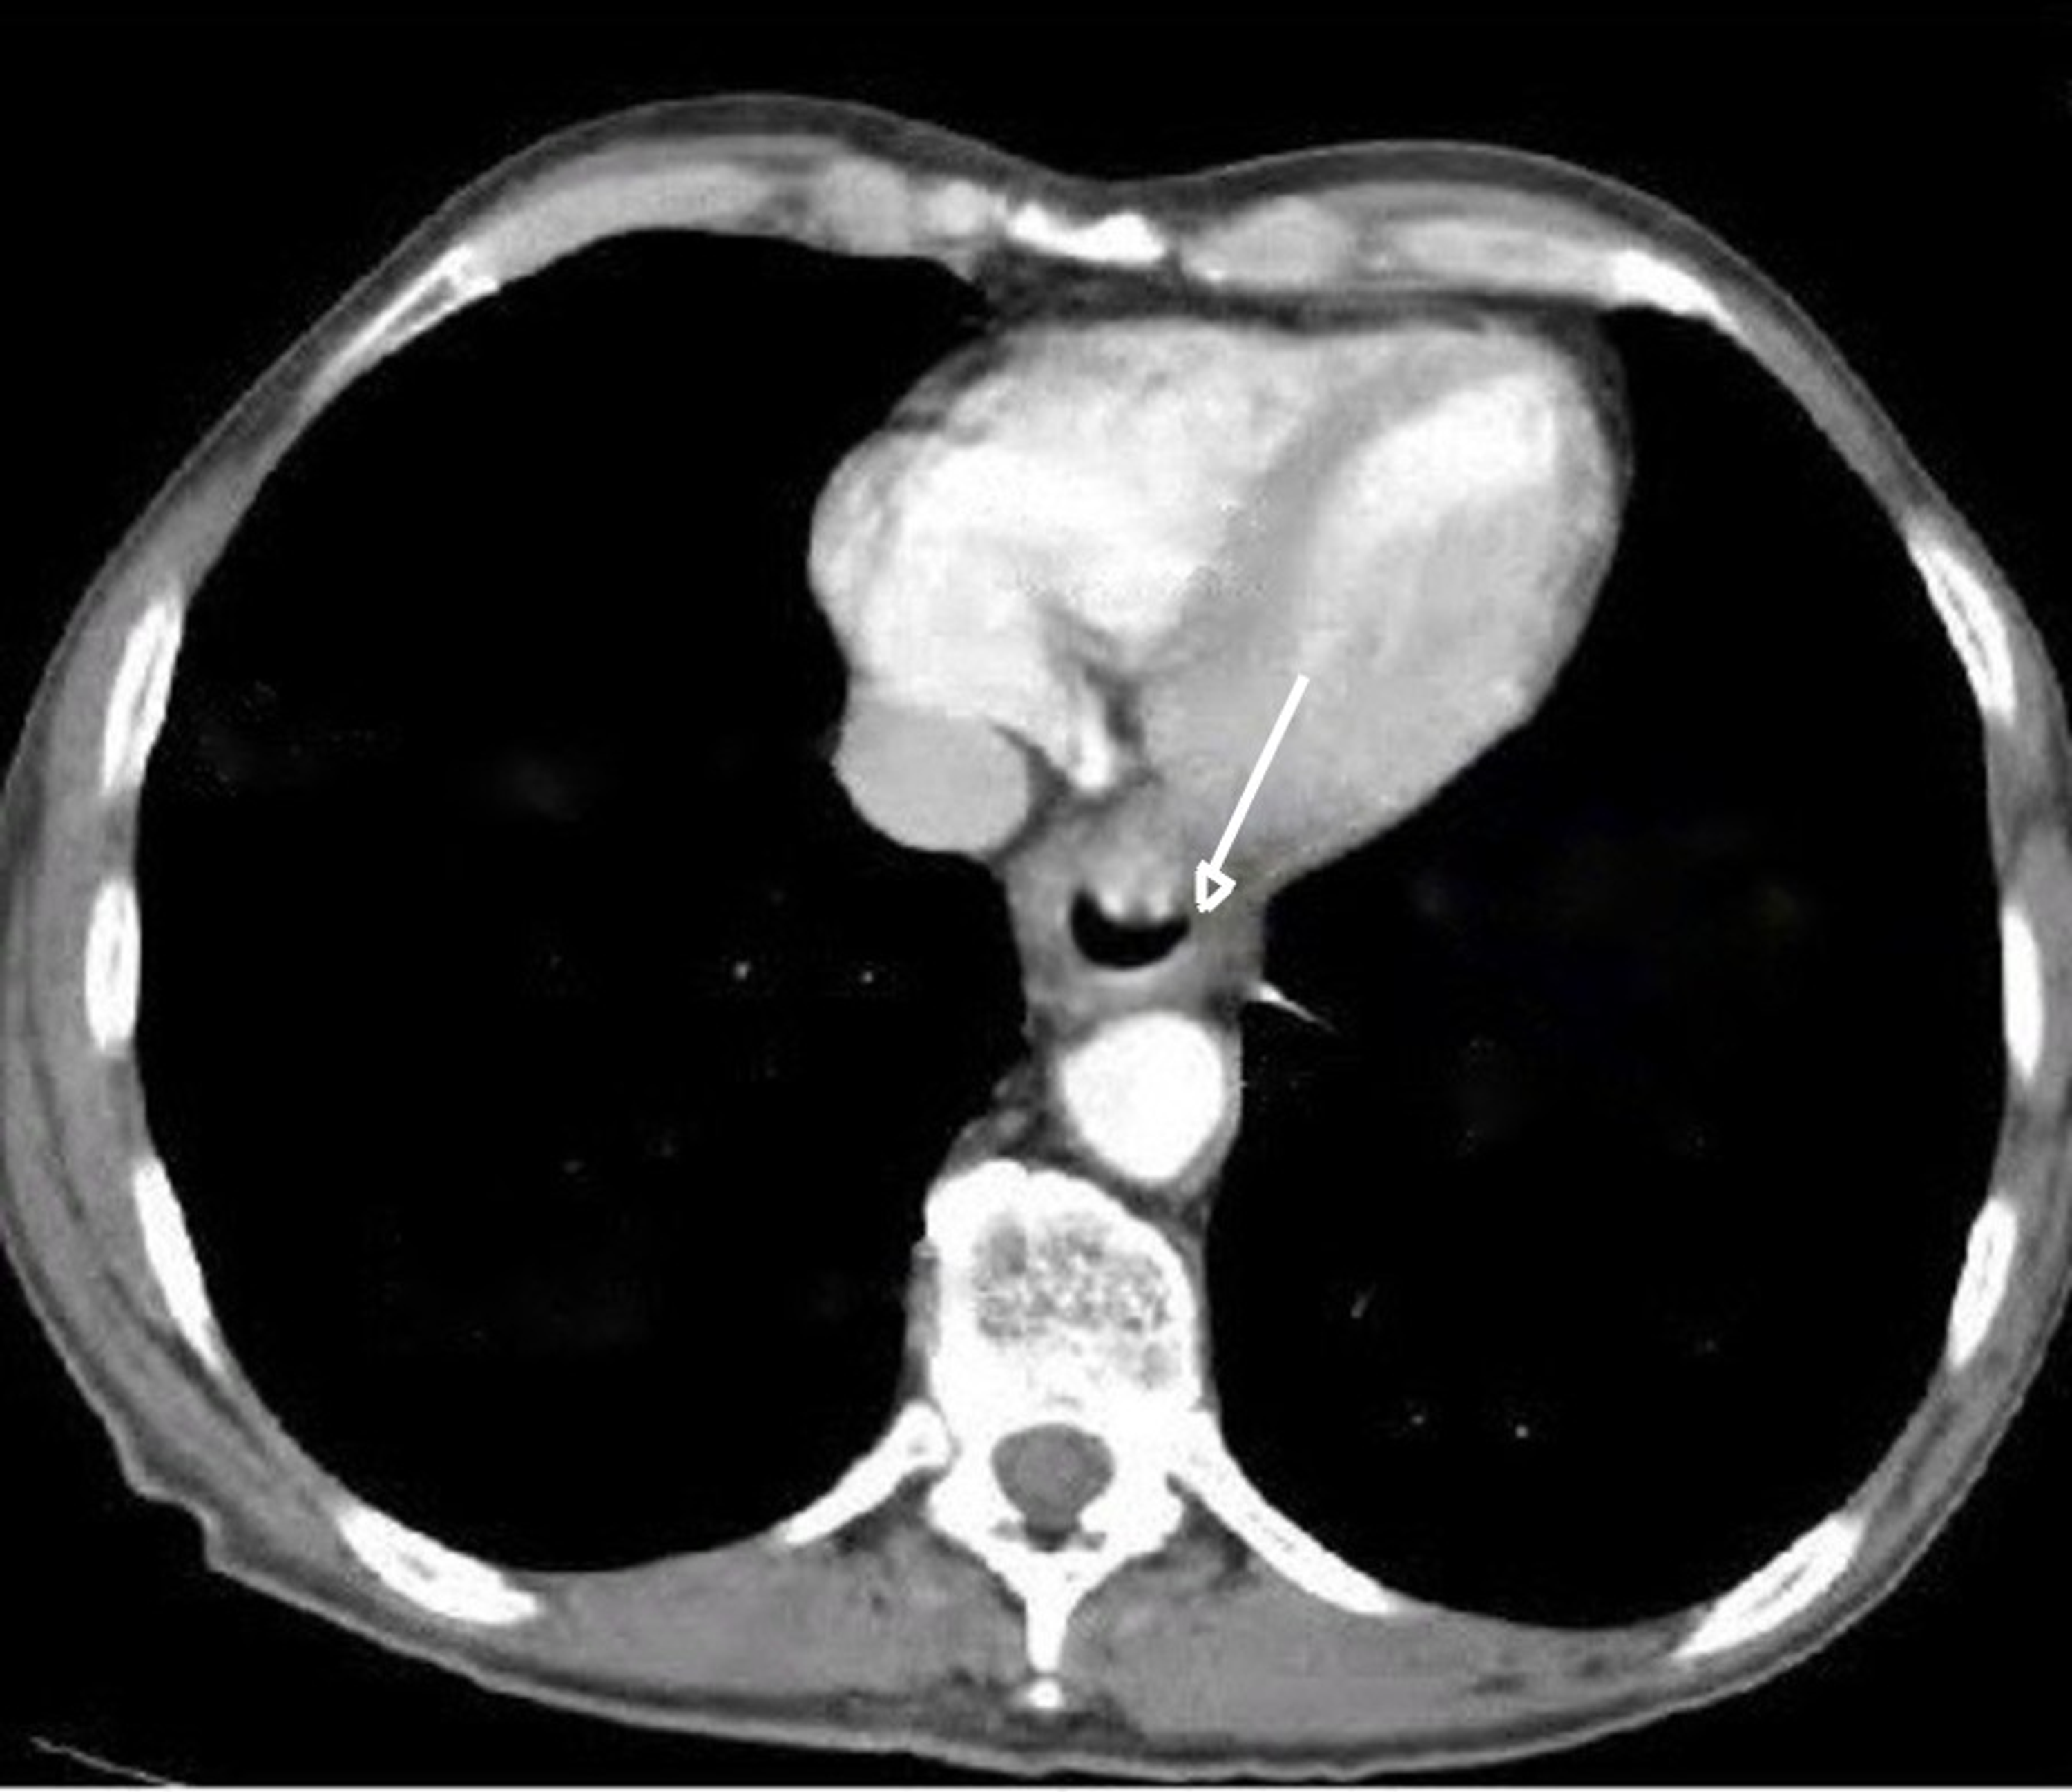

From www.researchgate.net

A typical case of esophageal neuroendocrine carcinoma. A Axial Neuroendocrine Cancer Esophagus esophageal neuroendocrine tumors (nets) are rare, aggressive and lacking specific symptoms. the clinicopathological features and optimum treatment of esophageal neuroendocrine carcinoma. to collect the cells, the doctor might insert a long, thin tube with a light and a camera on the end into your lungs. in total, 39 esophageal net were analyzed and 38 were neuroendocrine. Neuroendocrine Cancer Esophagus.